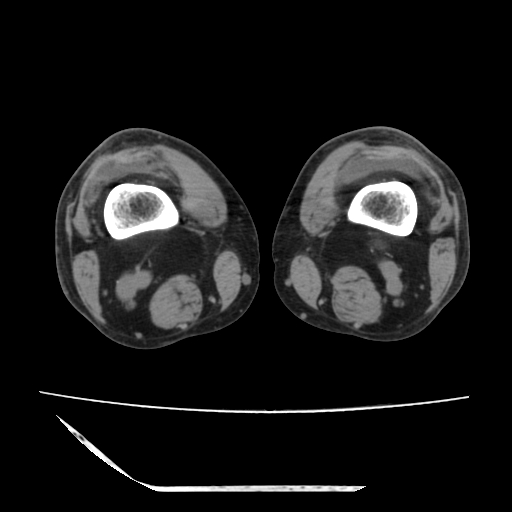

标题: CT13225:老年男性,左膝关节疼痛数月;请各位老师讨论。 [打印本页]

标题: CT13225:老年男性,左膝关节疼痛数月;请各位老师讨论。

骨质增生,骨性关节面硬化,关节积液,考虑退行性骨关节病

关节腔内少量积液,关节面退变。

双膝退变

骨质增生,骨性关节面硬化,关节间隙失常,关节积液,考虑退行性骨关节病.

骨质增生,骨性关节面硬化,关节积液,考虑退行性骨关节病。

这个病例诊断:退行性骨关节炎